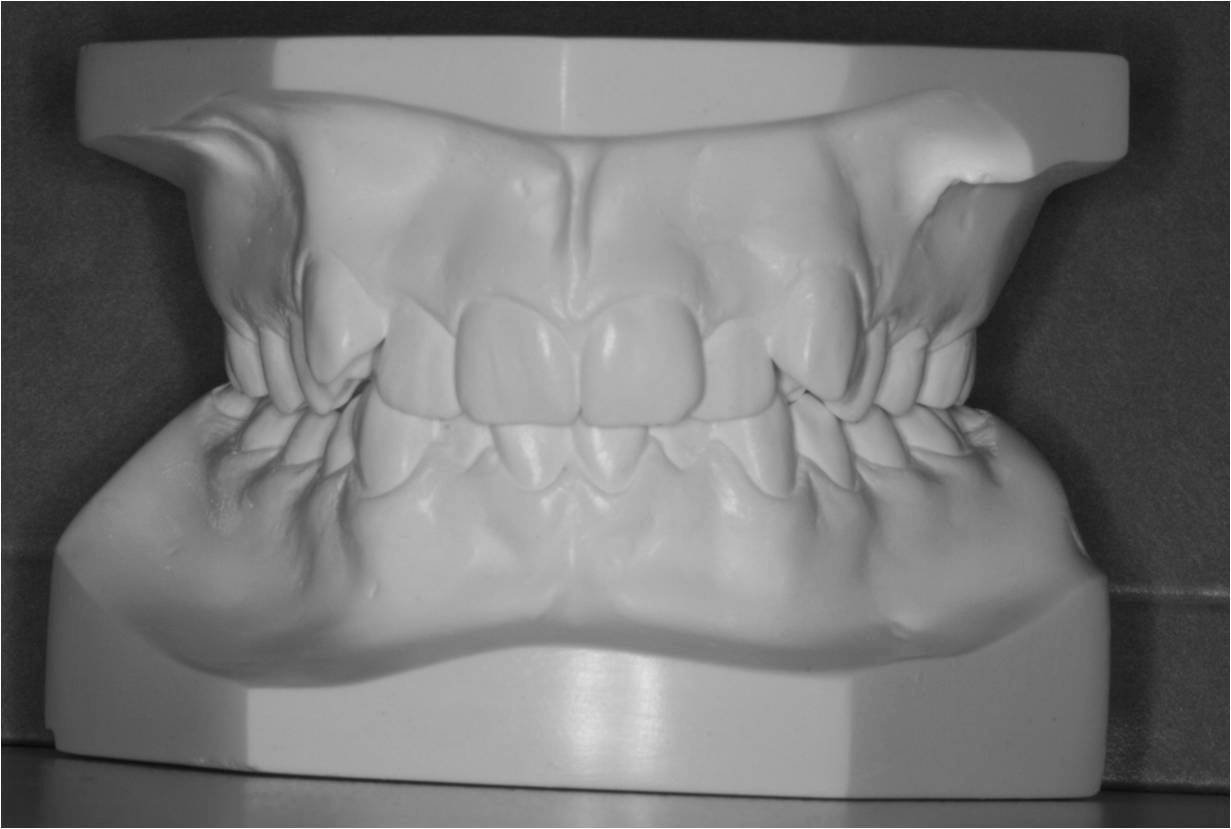

Studiemateriale, består af modeller, fotos og røntgenbilleder af tænder og ansigt. Der bliver også udleveret et helbredsskema, som skal udfyldes på stedet. Det er vigtigt at vide, om jeres barn er sundt og raskt, eller om der er særlige hensyn, vi skal tage - eksempelvis til medicin med videre.

Der bliver taget billeder "udenpå og indeni" samt røntgenbilleder.

Dit barn skal selv holde sine læber til side med en læbeholder, mens tænderne bliver fotograferet. Billederne har følgende formål: